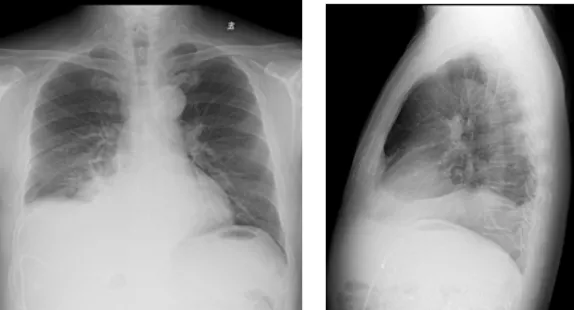

影像學檢查結(jié)果

右肺炎癥不能排除,請結(jié)合臨床。右側(cè)少量胸腔積液

右側(cè)胸腔積液細胞學檢查結(jié)果

(右側(cè)胸腔積液)細胞學檢查見少數(shù)惡性細胞,形態(tài)考慮腺癌細胞。